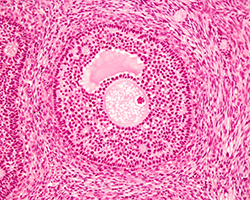

Genital Femenino

Genital Femenino

Ovario, trompa, útero, cuello, vagina y placenta.

(17 preparaciones) -